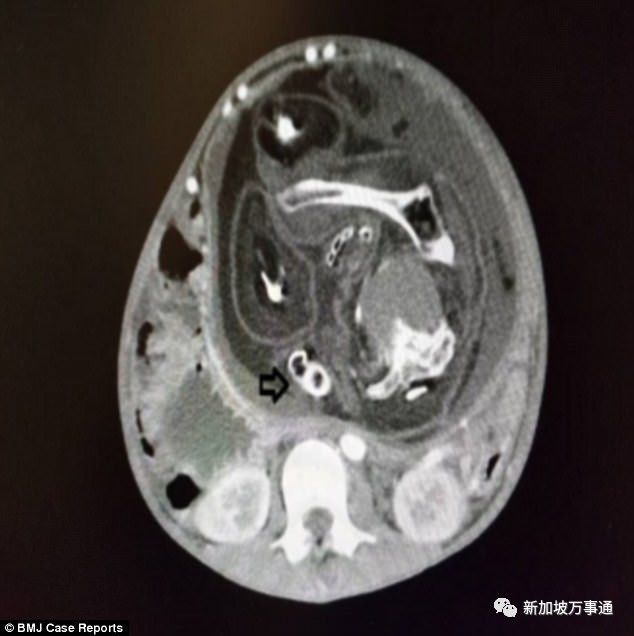

然而,就在少年做了CT后,整个事件就变得扑朔迷离,就连医生也感到震惊不已!——这个肿块中竟然发现了脊柱!

肿瘤的诊断马上就被*翻推**了,再检查后他们陆续的发现了肿块中可见的变形头骨、脊椎,这绝不是肿瘤,而是一个畸形胎儿!!!

来源:BMJ 案例报告

小编已经打码了,但是照片还是让人感到触目惊心。取出的“寄生胎”不是正常人形,看上去就是一个畸形的胎儿——有头发和生殖器官,但是四肢变形,没有口部、脐带或胎盘。

而且,在少年腹中的15年,这个寄生胎与少年共享血液系统,甚至,吸收着他的营养,越长越大......